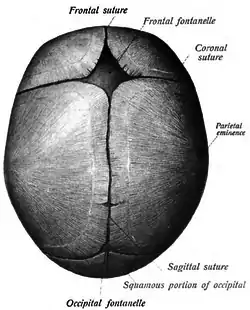

Sagittal suture

Human adult skull from above.

Human adult skull from above. Sagittal suture labeled at center.

The sagittal suture, also known as the interparietal suture and the sutura interparietalis, is a dense, fibrous connective tissue joint between the two parietal bones of the skull. The term is derived from the Latin word sagitta, meaning arrow.

The sagittal suture is formed from the fibrous connective tissue joint between the two parietal bones of the skull.[1] It has a varied and irregular shape which arises during development.[1] The pattern is different between the inside and the outside.[1]

Two anatomical landmarks are found on the sagittal suture: the bregma, and the vertex of the skull. The bregma is formed by the intersection of the sagittal and coronal sutures. The vertex is the highest point on the skull and is often near the midpoint of the sagittal suture.